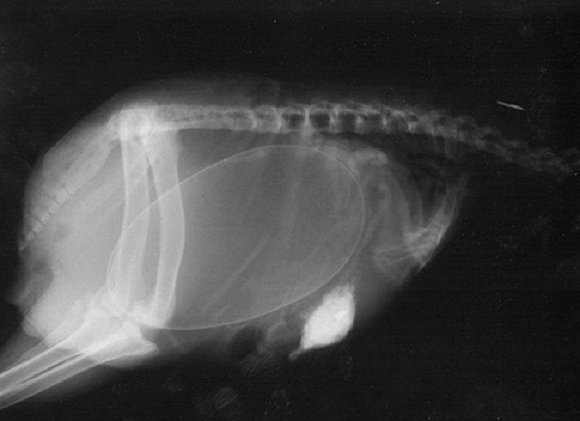

可爱又毛骨悚然 怀孕动物的X光片

人类之间分享母亲肚子里胎儿的X光片是一件非常常见的事情,但是,纵使你觉得自己对X光片已经见怪不怪,在看到了下面这些怀孕动物的X光片后你仍旧会说"哦我的天哪"。

以下就是一些动物在怀孕时的X光片。

4. 猫